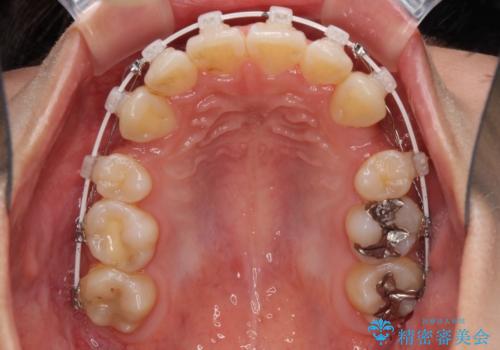

- 審美装置

- 2年3ヶ月

- 10-30回

半年ほどで前歯のデコボコは改善され、汚れの溜まりやすさは解消されました。

抜歯スペースを閉じるために期間がかかりましたが、当初予定通り2年強で終えることができました。